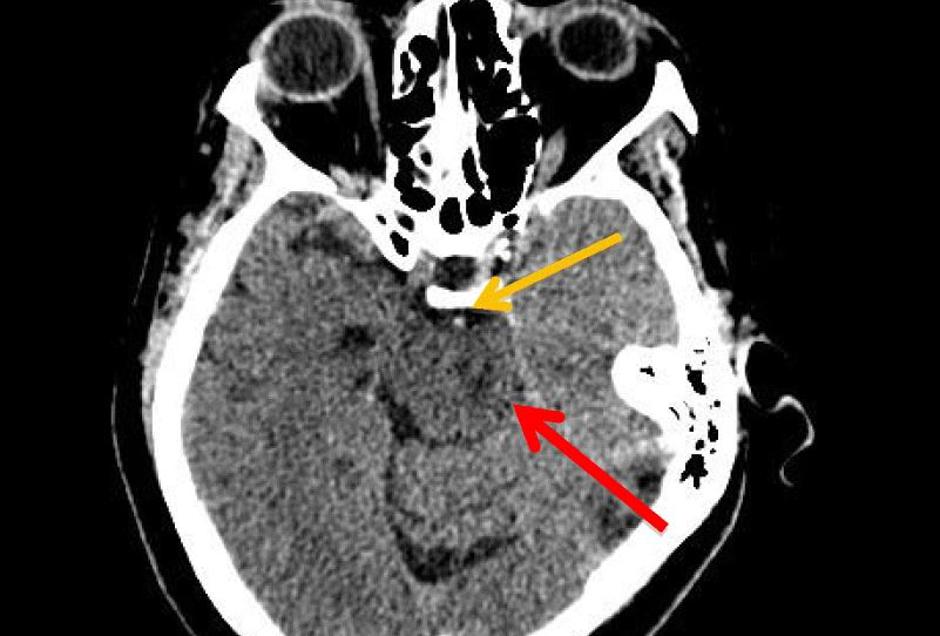

Štiri dni po uživanju kokaina je neimenovana Američanka iz Marylanda doživela možgansko kap, kar sicer ni nič nevadnega. Po navedbah zdravnikov, ki so svoj nenavadni medicinski primer opisali v znani strokovni publikaciji Journal of Medical Case Reports, je "uživanje kokaina dobro dokumentiran dejavnik pri ishemičnih in hemoragičnih možganskih kapi."

Kot navajajo zdravniki, je doživela sindrom zaklenjenosti, ki je redek pojav po možganski kapi. Ekipa zdravnikov z Medicinske fakultete Univerze v Marylandu verjame, da je imela ženska štiri dni po uživanju kokaina zapoznelo možgansko kap. Zaradi tega je njen primer prvi te vrste v znanstveni literaturi.

Sindrom zaklenjenosti je redka možganska motnja, ki povzroči popolno paralizo vseh mišic, razen tistih, ki nadzorujejo gibanje oči. Trpeči so zavestni, vendar ne morejo govoriti ali se premikati. Običajno je prizadeta njihova kognitivna funkcija.

| Avtor: BMJ BMJ

Povzroči  ga poškodba možganskega debla, ki vsebuje živce, ki prenašajo informacije na druge dele telesa. Takšna poškodba se običajno pojavi zaradi pomanjkanja krvnega pretoka ali krvavitve po travmi. Bolniki ne morejo žvečiti, pogoltniti, govoriti ali se premikati, razen oči, vendar lahko vidijo in slišijo. Večina prizadetih je na postelji in je odvisna od nege.